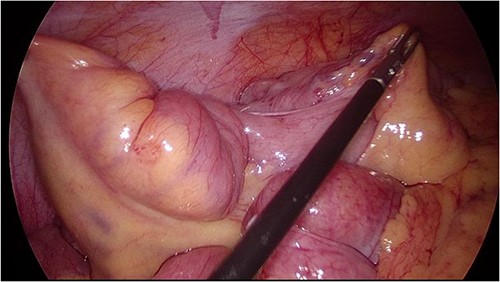

She then underwent an elective diagnostic laparoscopy which showed a cicatrizing small bowel mass in distal ileum ~15 cm from TI (Figs 3 and 4), with a normal appendix and no other abnormalities. There were no stigmata of endometriosis, and no free fluid or blood in the pelvis/abdomen. A wedge resection of the mass with a side-to-side small bowel anastomosis and planned removal of the appendix (due to pre-operative concerns of further adhesions in the area) was performed.

Intraoperative image at laparoscopy showing TI tethered down into cicatrizing mass. Foci of endometriosis on proximal large bowel.